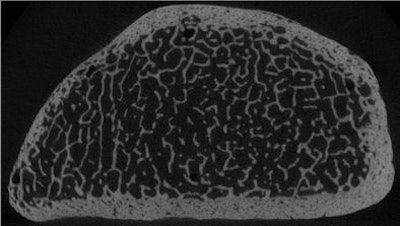

| Trabecular structure of the human radius bone at micro-CT, 18-µm spatial resolution. Image courtesy of Dr. Ahi Sema Issever and Dr. Patrick Rogalla. |